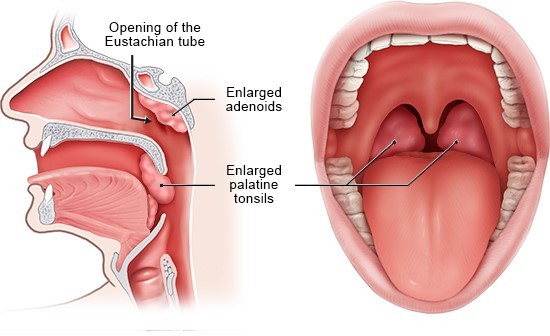

Overview

Package includes:

Days in hospital : 2 to 3 Days (For patient and one attendant)

Days in hotel : 7 Days (For patient and one attendant)

Room type in hospital : Shared

Room type in hotel : Private

Hotel category: Standard

Value added benefits of the Adenoidectomy: